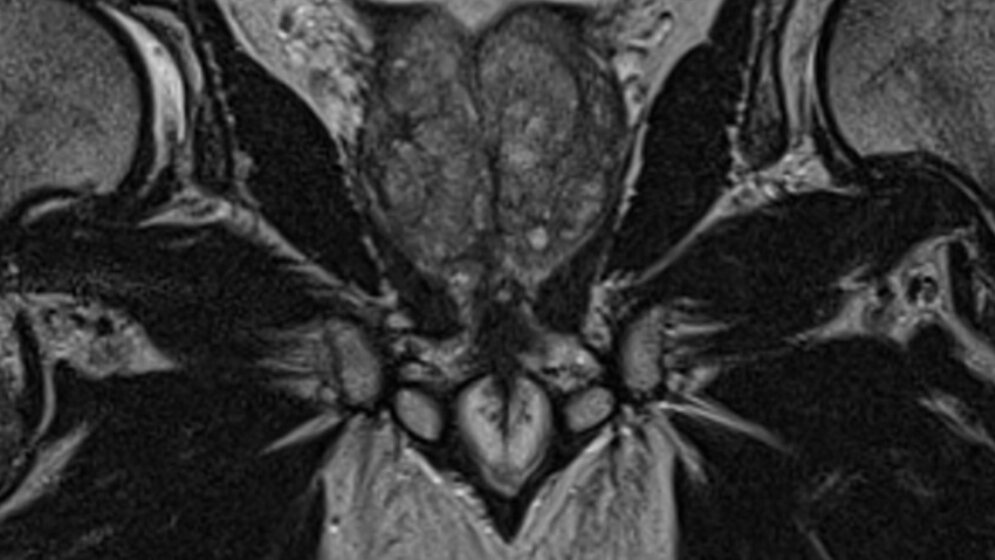

Die MRT-Untersuchung der Prostata ist in den letzten Jahren zu einem entscheidenden Verfahren zum Nachweis von klinisch signifikanten Karzinomen der Prostata geworden.

Der vorliegende Beitrag erläutert, wie mit diesem Verfahren Malignome und entzündliche Veränderungen der Prostata erkannt werden können. Die Untersuchung sollte immer als multiparametrisches MRT der Prostata gemäß der geltenden PI-RADS-2-Leitlinien durchgeführt werden und eine Diffusionswichtung, drei hochaufgelöste T2-gewichtete Sequenzen und eine Reihe von zeitlich hochaufgelösten dynamischen T1-Sequenzen umfassen,.